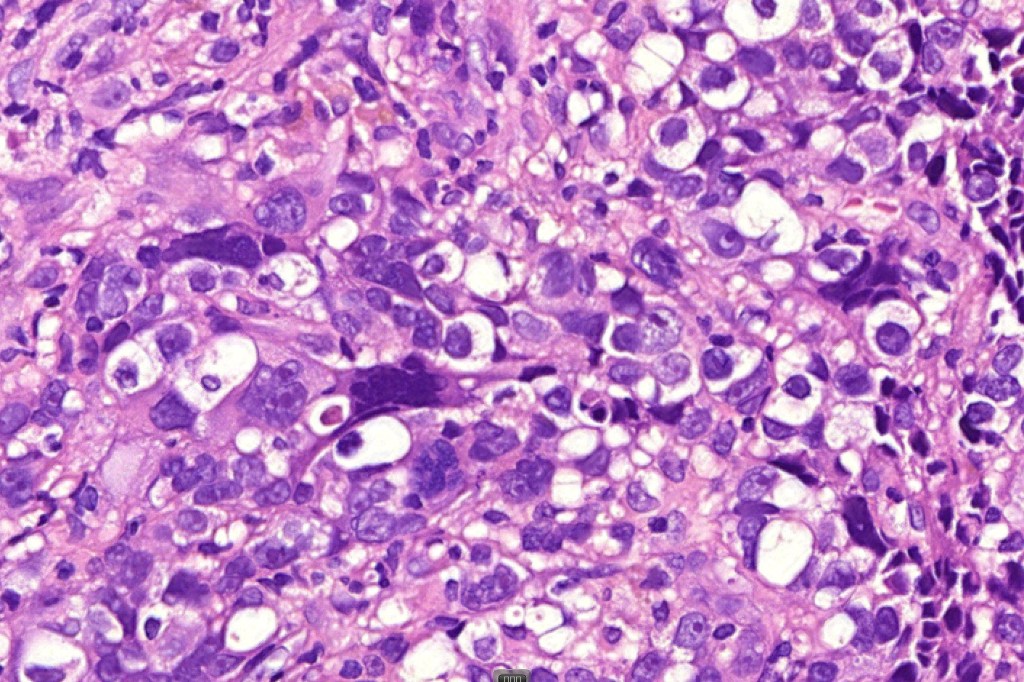

These are very rare variants of amelanotic or virtually amelanotic melanoma where a primary melanoma or a metastasis shows partial (DN) or complete loss (UN) of recognizable histological and immunohistochemical features. The histology may lead the pathologists to consider lymphoma, sarcoma, anaplastic carcinoma or a small cell tumor. Some examples of rhabdoid melanoma & melanoma with heterologous differentiation probably belong in this category. Ultimately, if there is no identifiable/recognizable primary tumor, diagnosis may only be comfortably made with next-generation sequencing. In the cases presented below, immunohistochemistry was of value in determining the melanoctic nature of the tumor (undifferentiated melanoma).